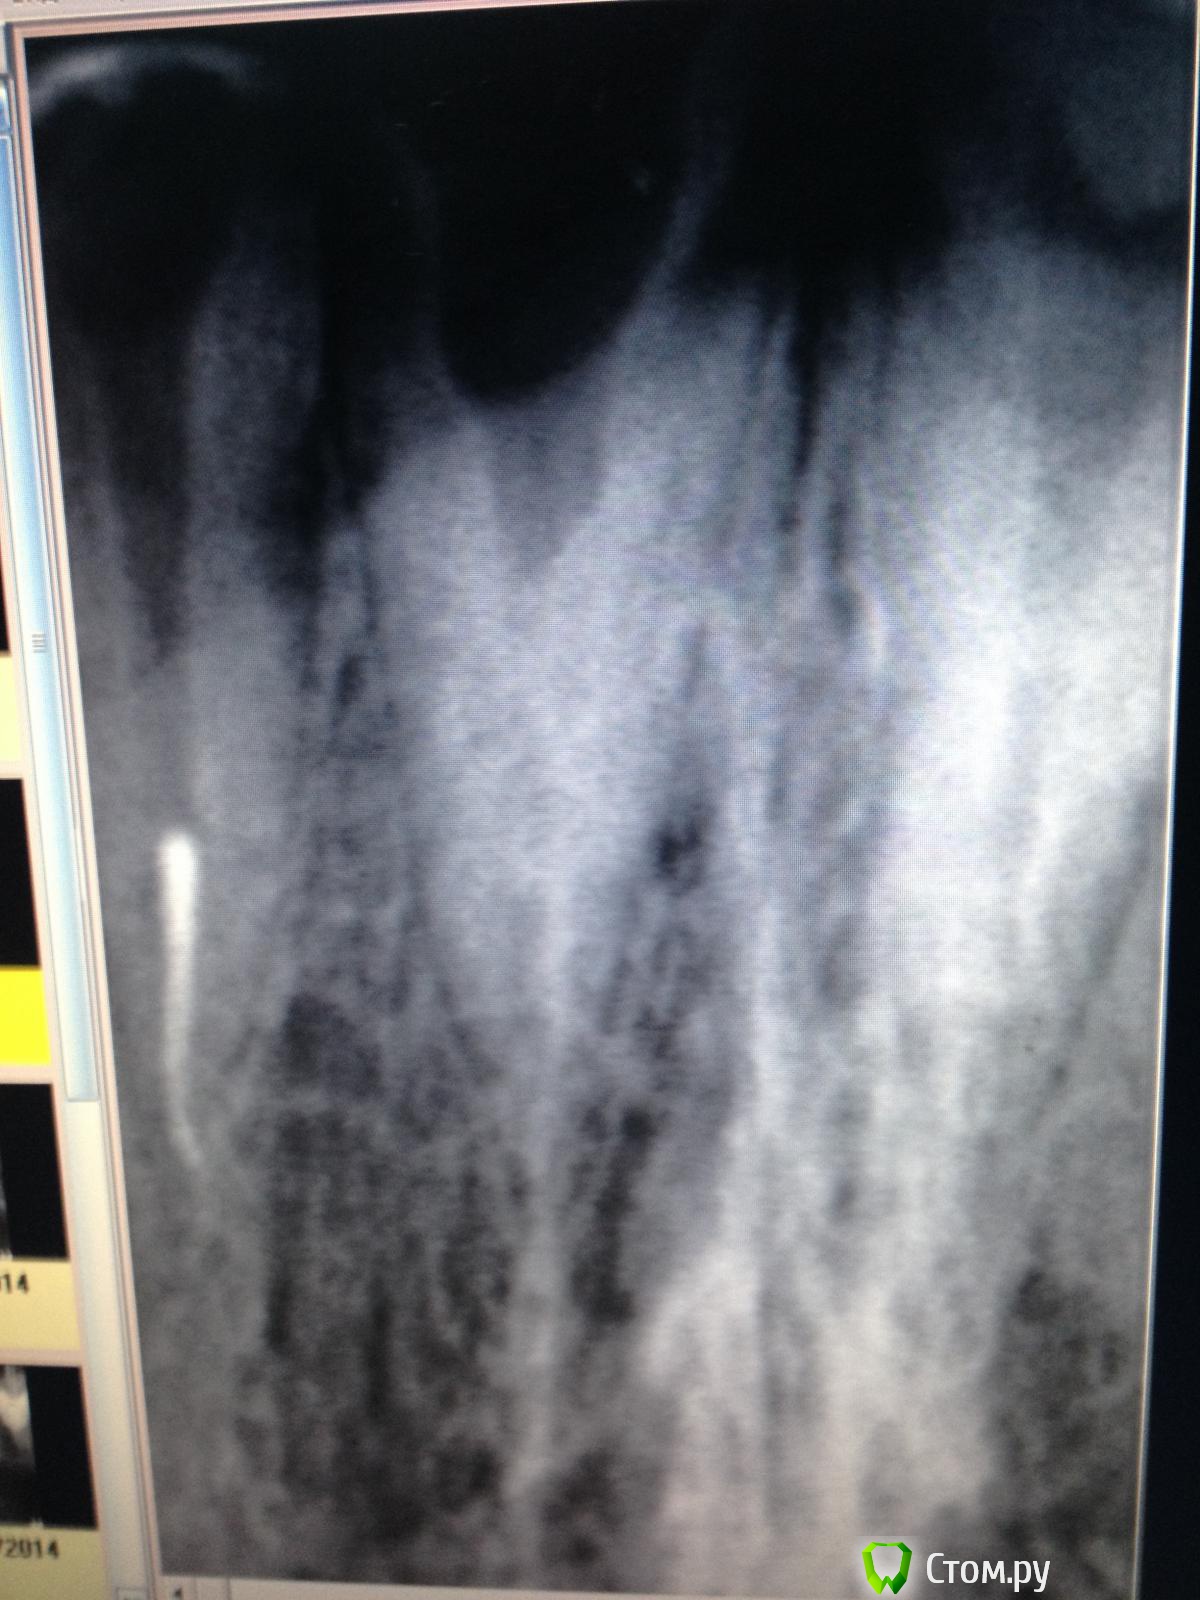

Ирина Игоревна Опубликовано 2 мая, 2014 Автор Поделиться Опубликовано 2 мая, 2014 IMG_20140502_182437 (1).jpgPANO_20140502_182342 (1).jpg Уважаемые форумчане, помогите советом!пациент отправлен ортопедом с целью протезирования. Планируется под вкладку. Ранее не лечен, но канал сильно склерозирован, не могу найти даже устье, ультразвуком билась, билась - не добилась, и хлоркой, лимонкой замыла, и RC-prep оставляла - ничего, самый тонкий 06 файл не идет, просвета канала на снимке не вижу. Потихоньку начинаю впадать в панику))))с соседними зубами таких проблем нет, везде первичное эндо Ссылка на комментарий

Ирина Игоревна Опубликовано 6 мая, 2014 Автор Поделиться Опубликовано 6 мая, 2014 как обещала, снимки. Ссылка на комментарий

ромашечка Опубликовано 6 мая, 2014 Поделиться Опубликовано 6 мая, 2014 К сожалению нет возможности отправить пациента, так что придется что то решать своими силами. Вроде ж получилось?) Это стираемость такая сильная или что? По снимку у меня ощущение эксперимента над безнадёгой) . Во рту наверное веселее? Ссылка на комментарий

Ирина Игоревна Опубликовано 7 мая, 2014 Автор Поделиться Опубликовано 7 мая, 2014 Вроде ж получилось?) Это стираемость такая сильная или что? По снимку у меня ощущение эксперимента над безнадёгой) . Во рту наверное веселее?Нет к сожалению, это пока соседние зубы готовим))а этот ждет...))стираемости нет, ткани зуба ушли во время некрэктомии, планировалось под вкладку. Причем в соседних зубах таких проблем нет (тьфу тьфу) А во рту напоминало дентикль, думала сейчас я его быстренько ультразвуком выбью, и всё а оказалось вовсе и не быстренько, да и не выбила Ссылка на комментарий